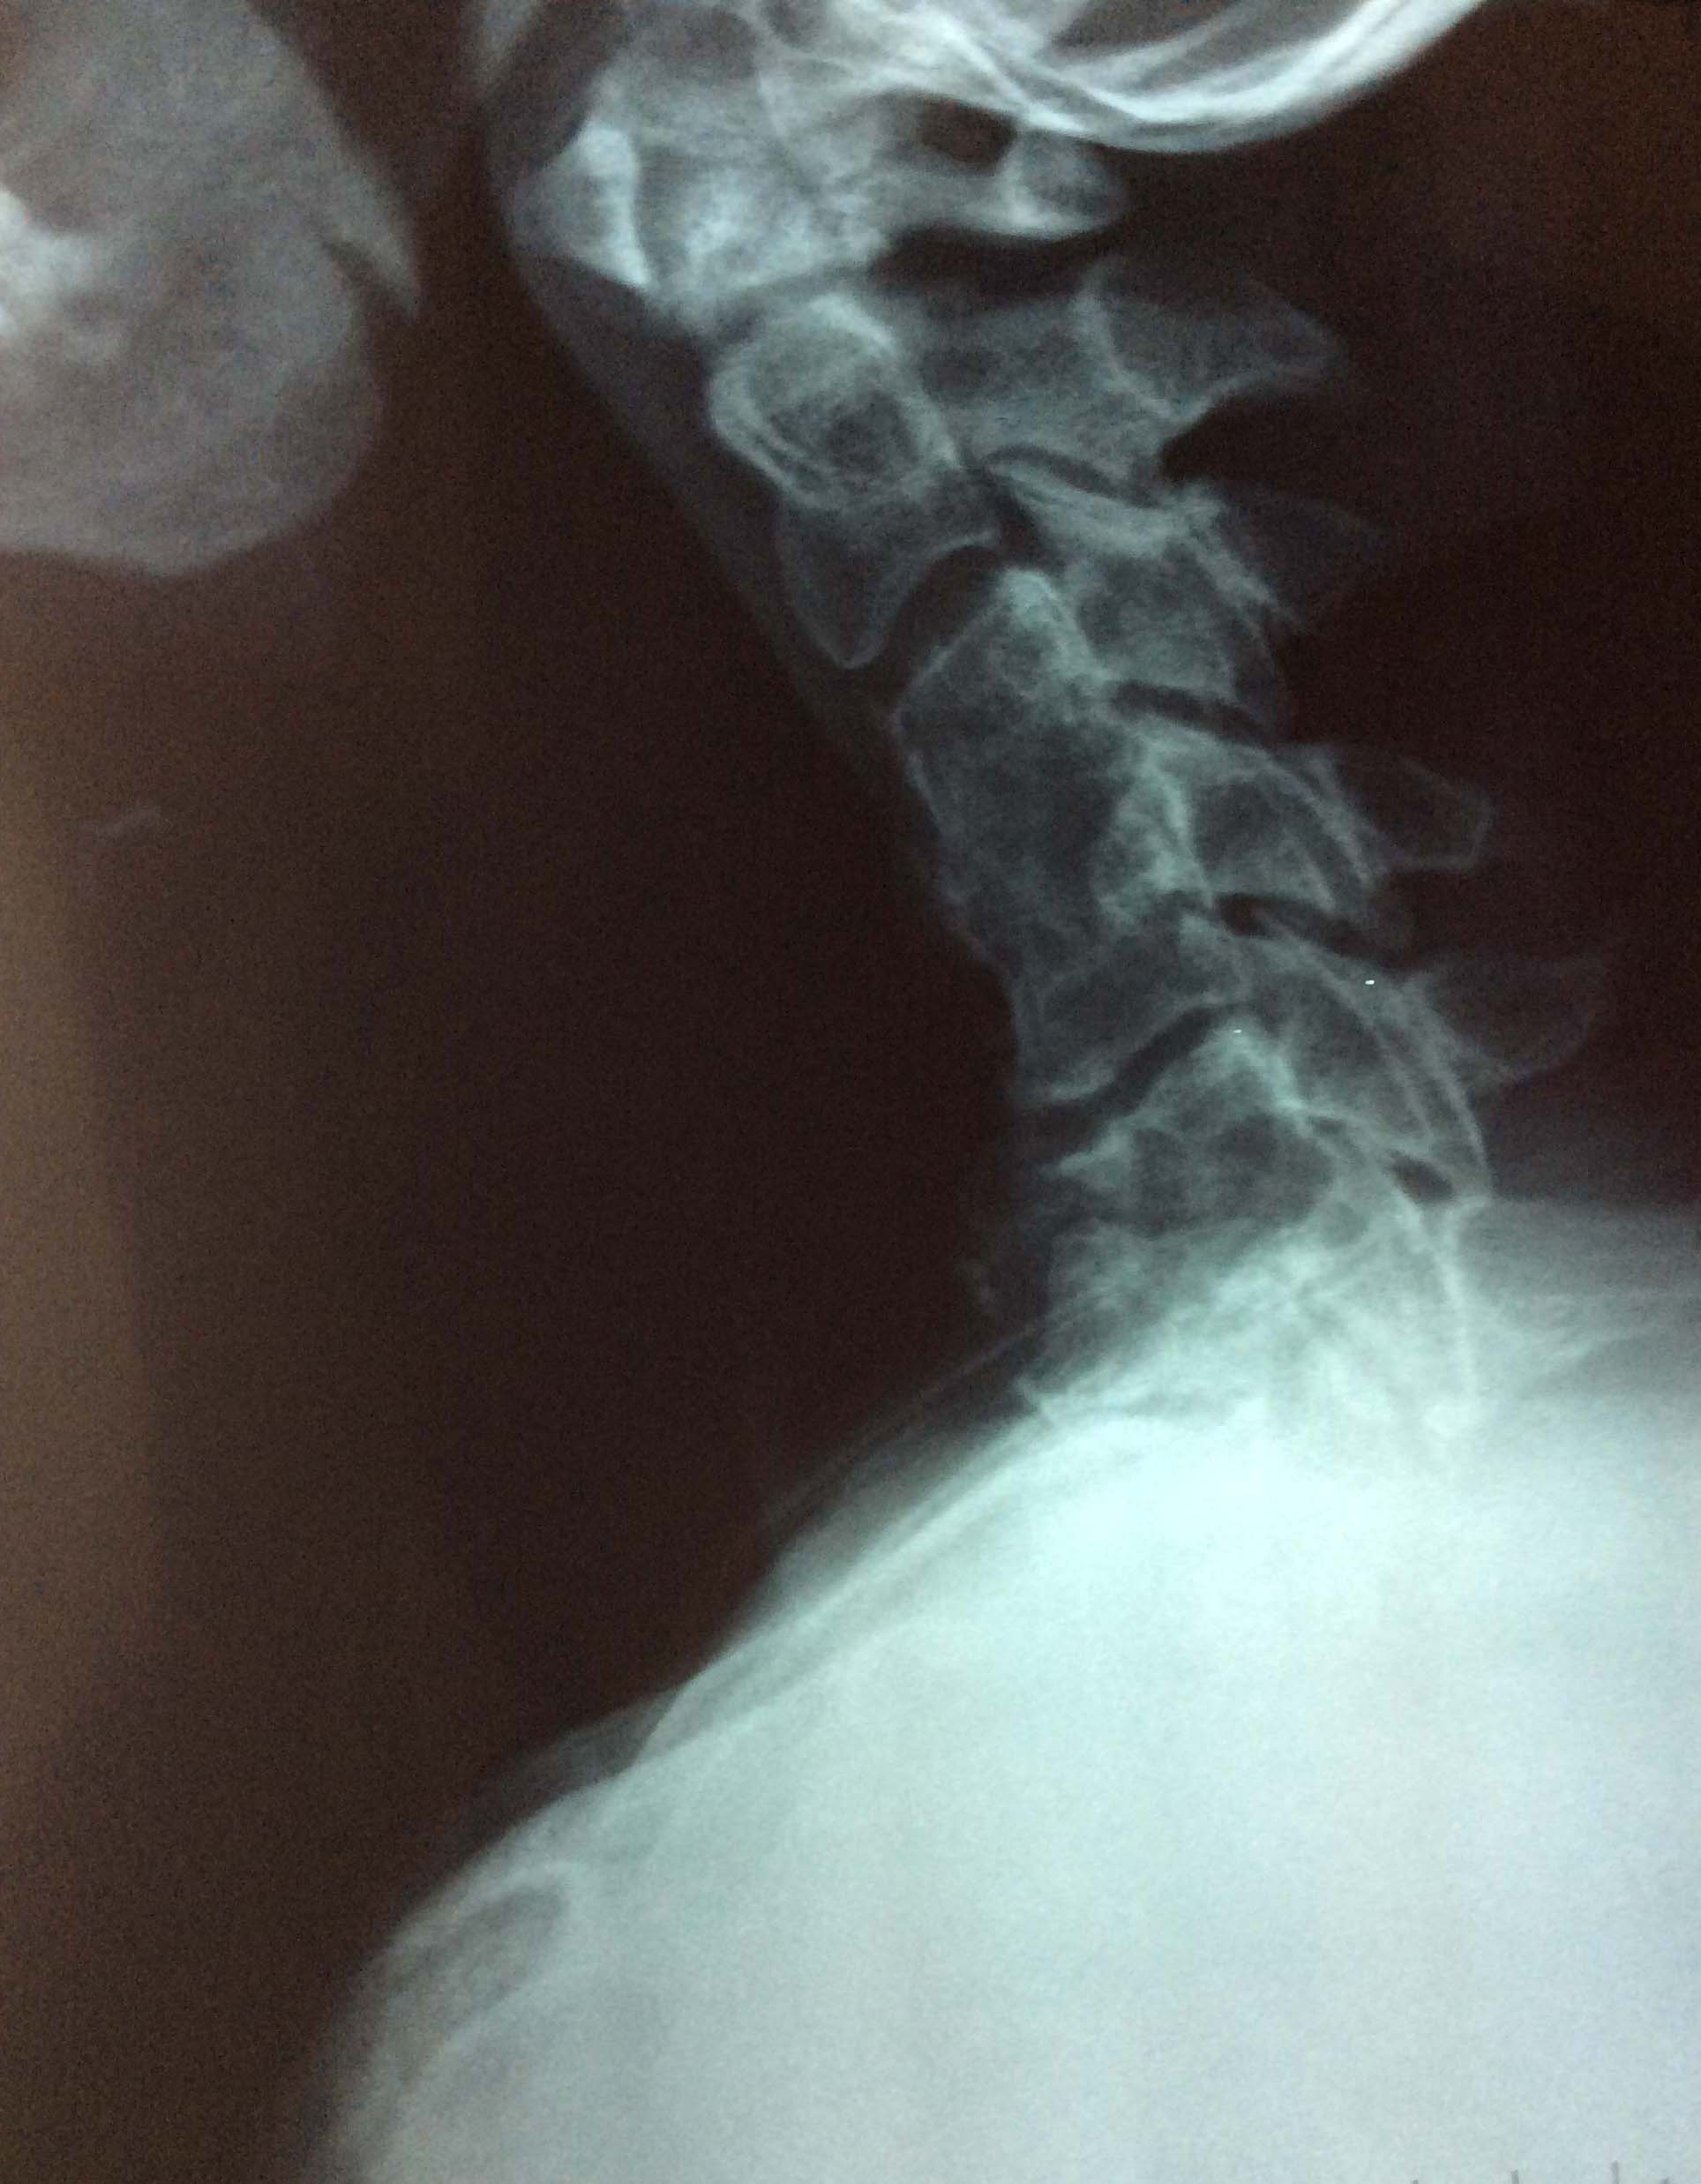

Εικόνα 1 (α,β,γ).

α : Πλάγια ακτινογραφία ΑΜΣΣ σε ουδέτερη θέση.

Παρατηρείται :

–  Η ΑΜΣΣ είναι σε κάμψη.

–  Υπάρχει αυτόματη οστική σπονδυλοδεσία του 3ου με τον 4ο αυχενικό σπόνδυλο.

–  Ο αυχενικός σπόνδυλος έχει ουσιαστικά καταστραφεί και γωνιωθεί το σώμα του δε είναι ενωμένο με το σώμα του 6ου σπονδύλου.